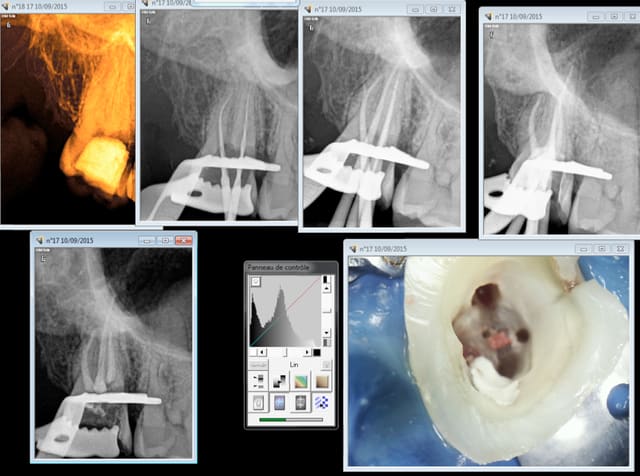

Et rien à changé : patient vu en "urgence " à la fac cet été : 1 H ouverture chambre et 2 canaux de trouvés -)))))

30 mn plus tard au cabinet ( et je sais encore trop de radios) .........-))))